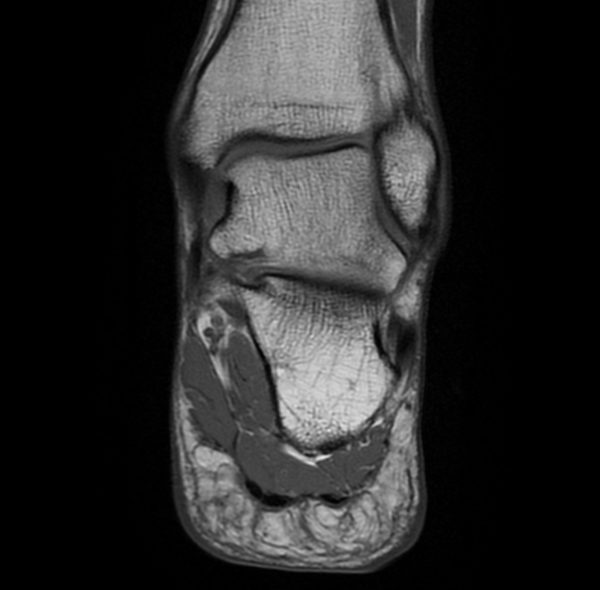

MRT OSG cor T1 gesund